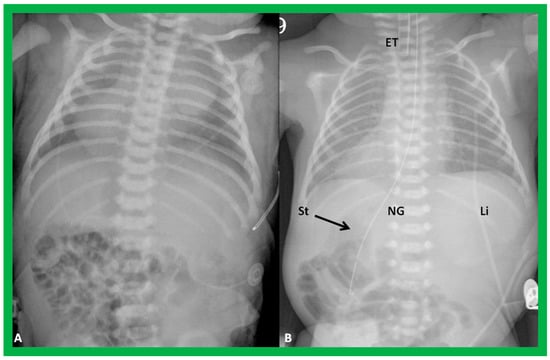

Figure 2. Chest X-rays of two different newborn babies with hearts situated in the right chest, i.e., dextrocardia. (A) The liver (Li) is visualized across the abdominal cavity without seeing the stomach air bubble; thus, it is not possible to establish the visceral situs. (B) On the other hand, the stomach (St) air shadow is faintly seen on the right side of the abdomen while the Li is imaged on the left side. The findings in (B) indicate inversion of the visceral position, situs inversus. Furthermore, the location of the St on the right is established by the location of the NG (nasogastric) tube. Air in the intestine is seen in the lower portion of the abdomen in both infants. ET, endotracheal tube. Reproduced from reference [4].

To utilize the principle of visceroatrial concordance, the locations of the liver (by its whitish opacity) and stomach (by its black gaseous opacity) should be visualized in posteroanterior view of chest radiographs (Figure 1, Figure 2B, Figure 3, Figure 4B, Figure 8, Figure 10 and Figure 11). Occasionally, the stomach bubble may not be present on routine chest X-rays (Figure 20A). In such situations, reviewing all the available chest X-rays (Figure 20B) or even injecting small quantities of air or barium (Figure 21) via a nasogastric tube may be warranted. However, the authors have not resorted to this since some chest X-rays exhibited a gaseous stomach bubble (Figure 20B).

Figure 20. Value of stomach (St) gas shadow in determining situs localization is shown in this figure. In (A), the St gas bubble was not seen, and therefore, visceral situs could not be classified. In a subsequent chest X-ray (B), the St gas was seen, indicating situs inversus. This case exemplifies the requirement for seeing the St gaseous opacity on the chest X-ray. Li, liver. Modified from reference [3].